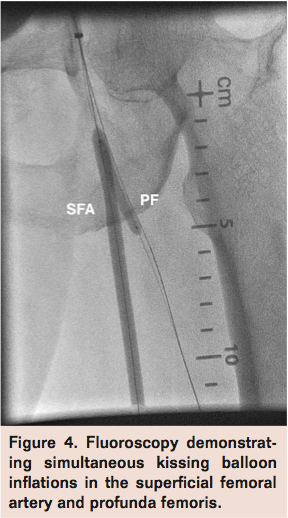

A 4 x 20 mm Sterling Balloon Dilatation Catheter (Boston Scientific) was then inflated distal to the thrombus in the PF and retrieved along with the guiding catheter to trap any embolic material between the balloon and the guide (Figure 2). Finally, the AngioJet catheter (Bayer HealthCare Radiology & Interventional) was advanced over the V-18 wire into the PF and SFA for rheolytic thrombectomy (Figure 3). Subsequent angiogram revealed moderate improvement in flow with persistent thrombotic material in both PF and SFA. A 6 x 100 mm Sterling Balloon Dilatation Catheter and a 4 x 30 mm Sterling Balloon Dilatation Catheter were then used to perform simultaneous kissing angioplasty of the SFA and PF respectively with good expansion (Figure 4). Final angiogram revealed significant improvement in flow through the SFA and PF segments with minimal residual thrombotic debris that were non-flow limiting (Figure 5). The patient was noted to have clinical reperfusion of his left lower extremity with resolution of symptoms, and he was discharged on hospital day 17 with a 6-week course of intravenous antibiotics.